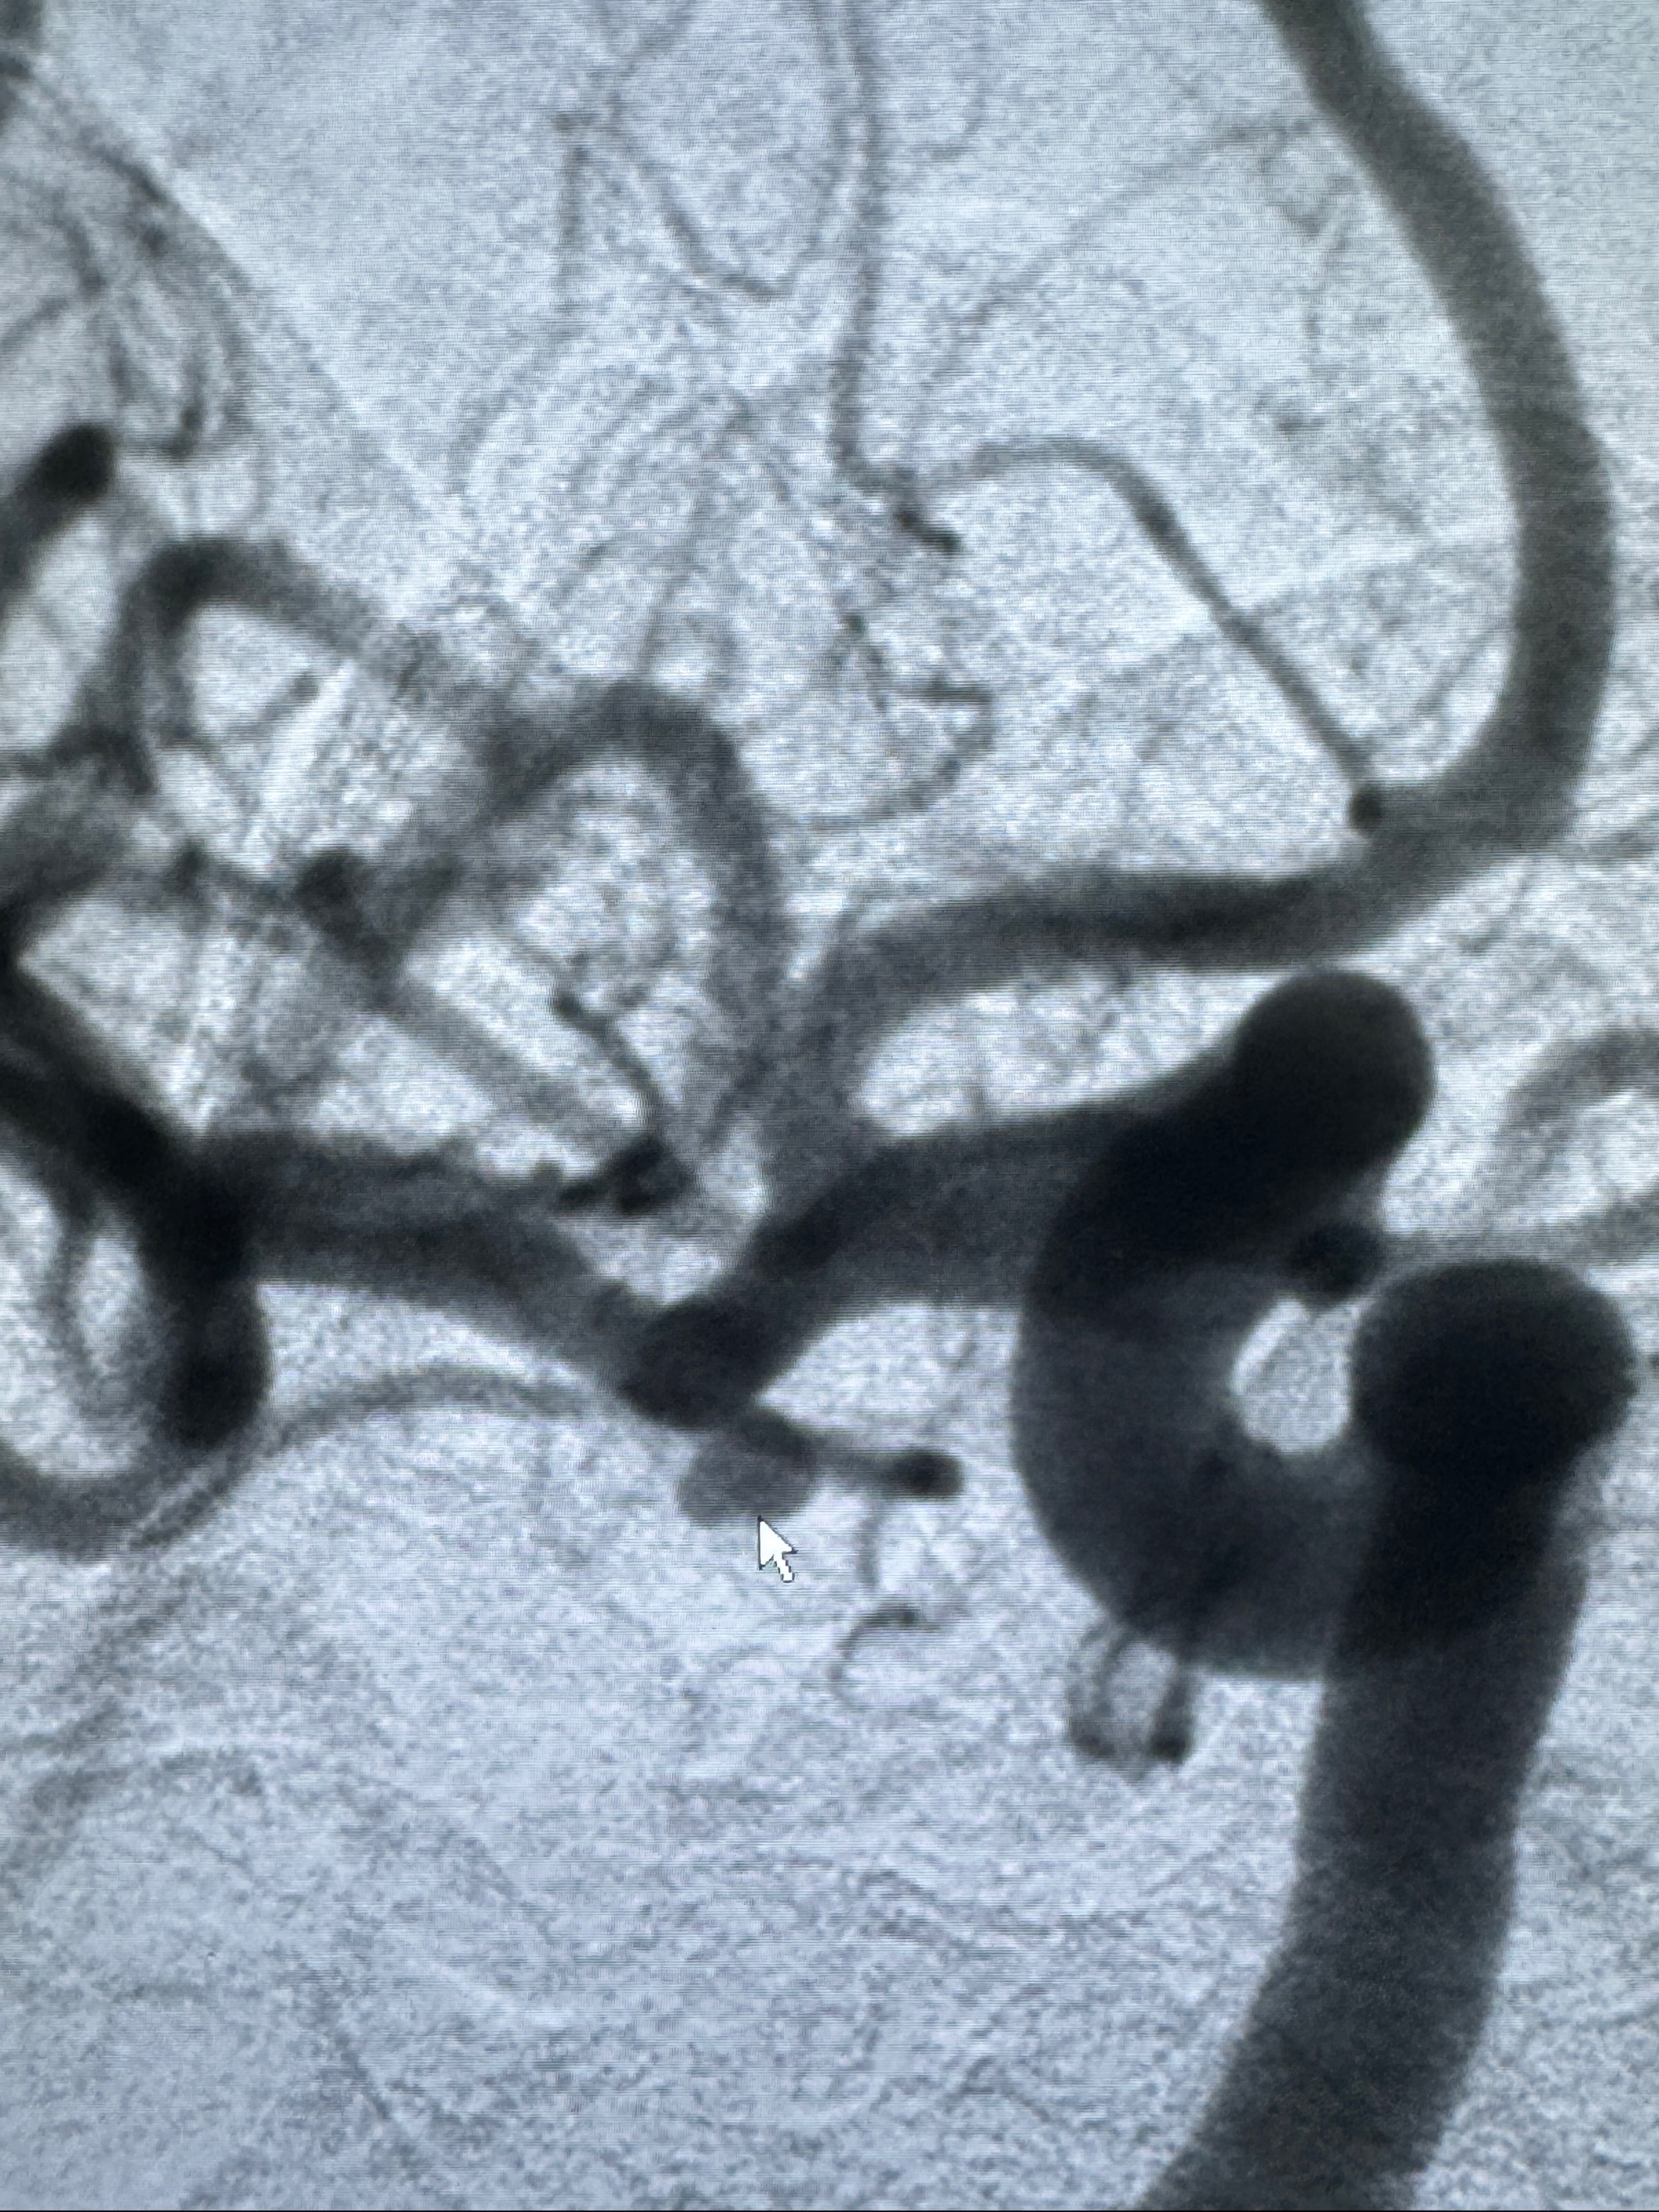

2023-11-24DSA:右侧大脑中动脉下干起始部动脉瘤,约2.3*2.5mm,形态规则

治疗策略:

- 随访?

- 夹闭?

- 单弹簧圈填塞?

- 支架辅助治疗?

2023-12-04全麻下行支架辅助治疗

S-AB4-20mm